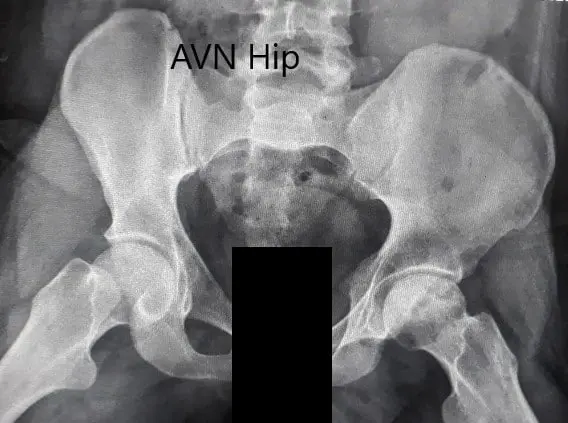

Imaging studies obtained in the form of an X-Ray suggested sclerosis of the left head of the femur. There were marked acetabulum changes. An MRI was further obtained suggesting avascular necrosis of the superior lateral head of the femur with changes in the acetabulum. There was marked hypointense areas on both T1WI and T2WIs.

Preoperative X-ray of the pelvis with both hips in anteroposterior view showing AVN of the Left Hip

Preoperative X-ray of the pelvis with both hips in anteroposterior view showing AVN of the Left Hip.